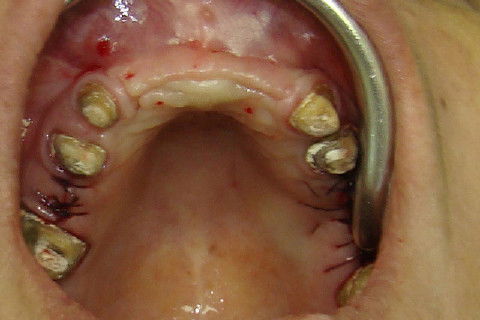

Vista oclusal da região anterior da maxila, antes da reabertura

Incisões horizontais e verticais para expor os implantes

Rebatimento do retalho e exposição dos implantes